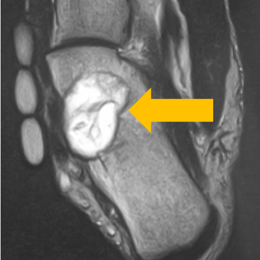

Radiographic imaging is used to help form a diagnosis of CMF. These include, X-Ray, MRI, CT and Bone Scans. An example of a CMF MRI is shown.